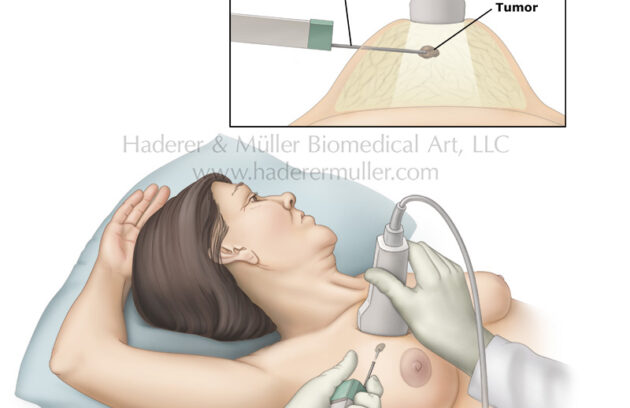

Totul despre puncția mamară ghidată ecografic

Ce este puncția mamară sub ghidaj ecografic? Puncția mamară sub ghidaj ecografic este o metodă minim invazivă prin care se…